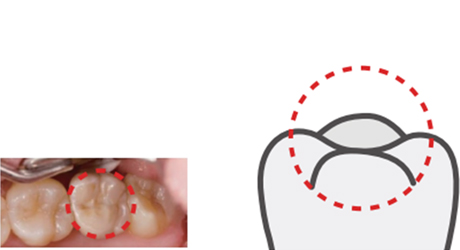

접착형 보철

접착형 보철보철물을 의료용 접착제로 부착하여 고정시키는 형태로 나사 연결식 형태보다 심미적입니다. 다만 잇몸에 접착제가 노출될 가능성이 있으며 보철물이 들뜨는 경우 아예 보철물을 제거하여 다시 제작하여 부착해야 합니다.

접착형 보철

접착형 보철